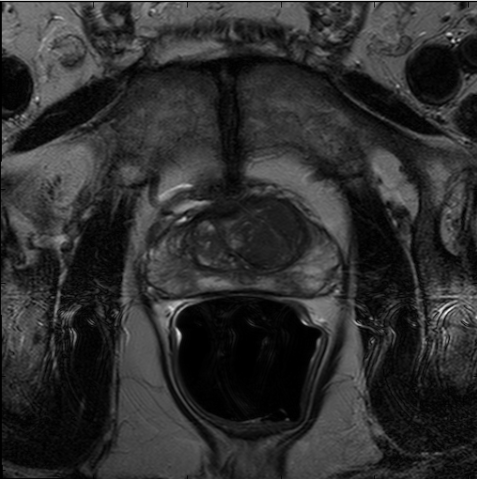

We trained our network on 77 patients. The input images and the manual ground truth annotation are shown in Fig.4. As we have described above, these images were acquired from different patients, and these images include the clinical variability. To evaluate our method, we randomly selected 4 patients with 64 images before training. These images do not take part in training and the prostate has been manually pre-delineated by a radiologist, which were used as the ground truth to evaluate the performance of automatic segmentation. We also selected dice coefficient as the evaluation method[30]. And to validate our method against U-Net and fully convolutional networks (FCNs), we used the same dataset to train and test the U-Net and FCNs.